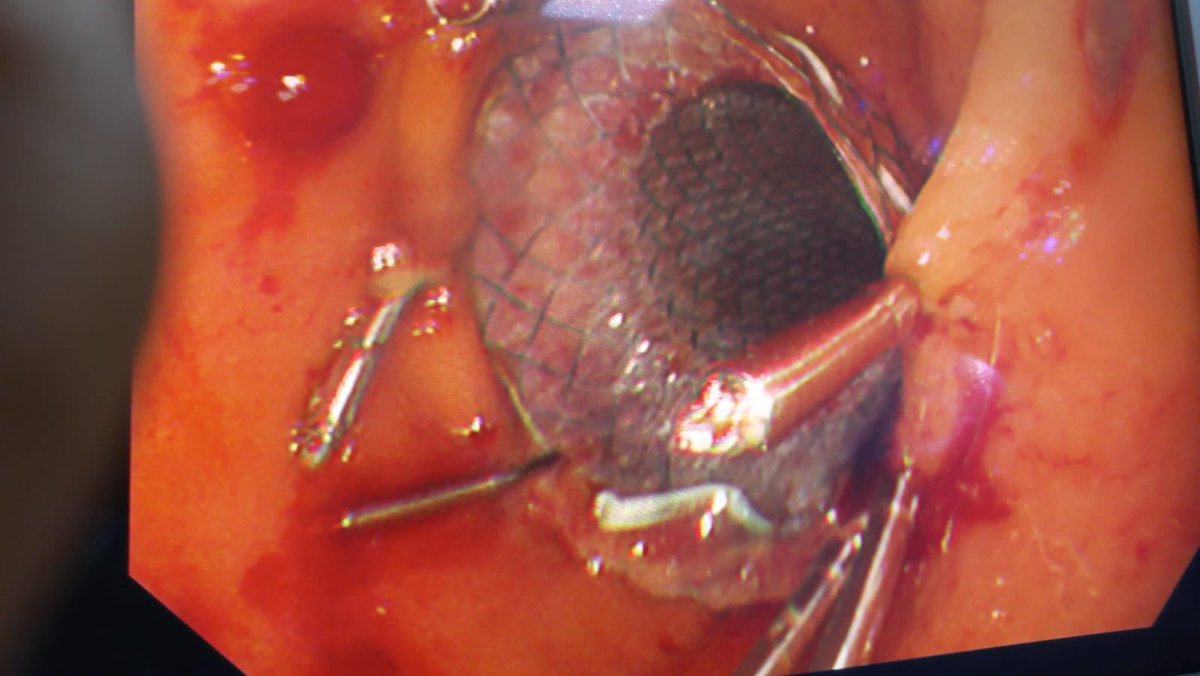

بالمنظار والتعاون الجراحي: وضع دعامه في الامعاء الدقيقة وتثبيتها بالدبابيس من خلال المنظار